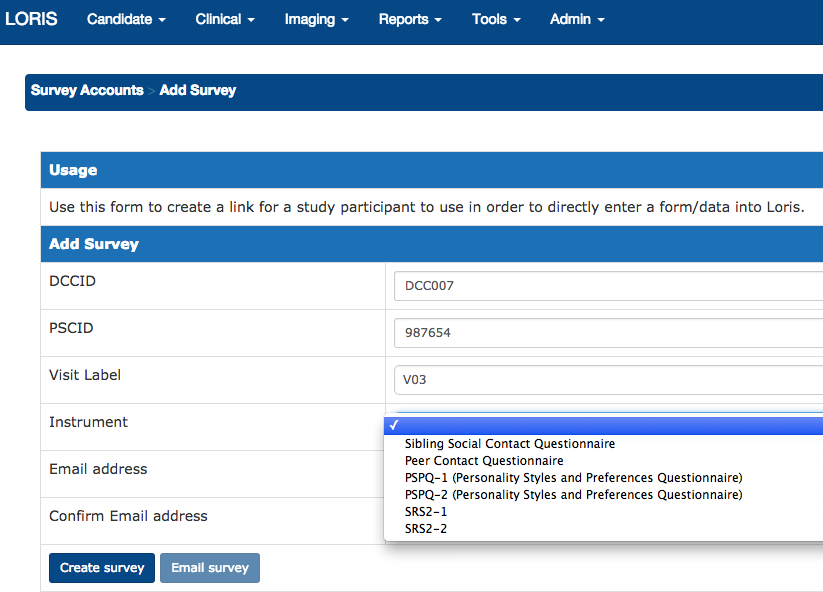

Survey Module

Tablet Friendly - Survey module